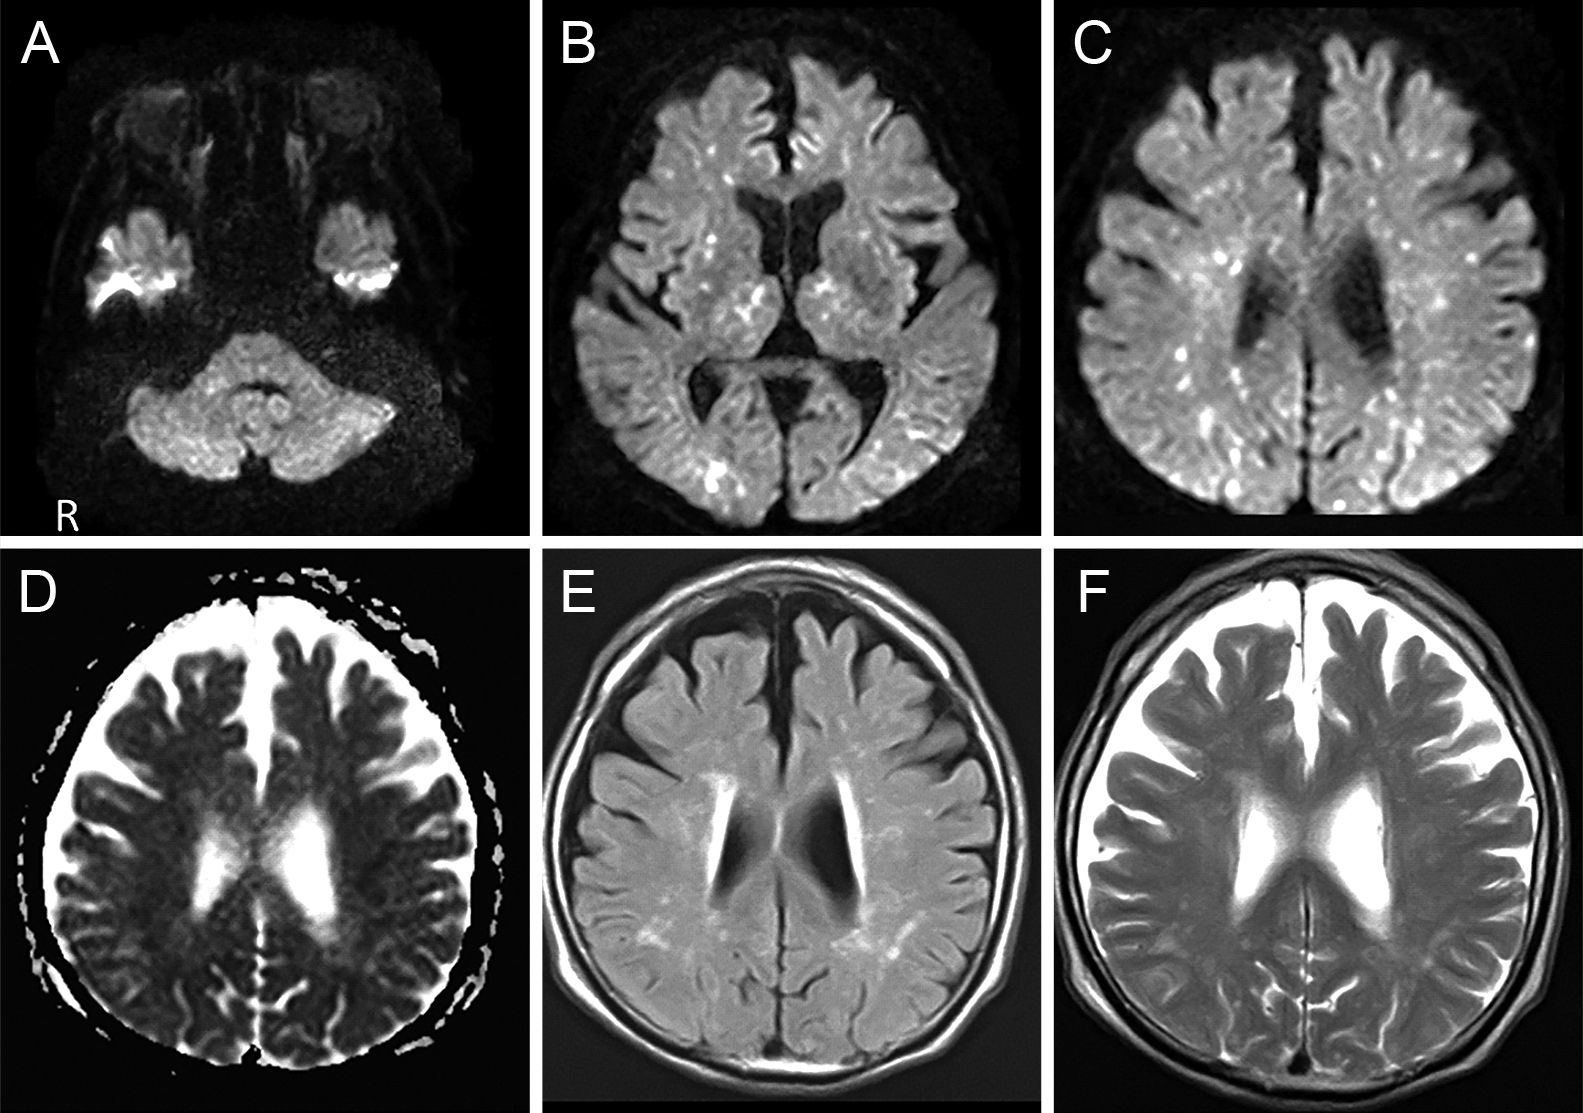

Claustrum signを呈したfebrile infection related epilepsy syndrome(FIRES)の55歳女性例

Febrile infection-related epilepsy syndrome (FIRES) with the claustrum sign in a 55-year-old woman: a case report

赤尾 剛, 市川 大, 藤盛 寿一, 中島 一郎

Go Akao, Dai Ichikawa, Juichi Fujimori, Ichiro Nakashima

2026/03/11